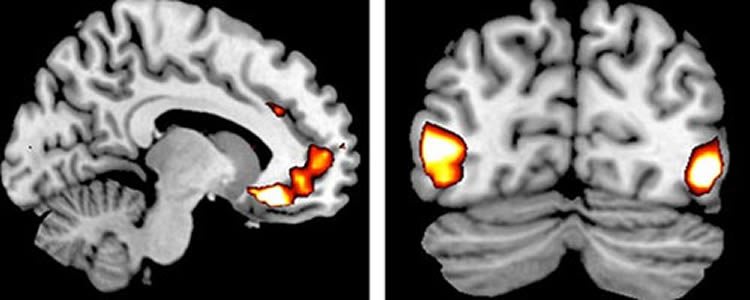

Die folgende Grafik zeigt funktionelle Magnetresonanz-Tomographie Aufnahmen von Hirnregionen, in denen Ser1A-Rezeptoren,

Ser1B-Rezeptoren, Ser2A-Rezeptoren und MAO A Enzyme am häufigsten lokalisiert wurden:

Copyright � 2016 by J Neurol Neurochir Psychiatr, Heft 1, 2016, S. 18.